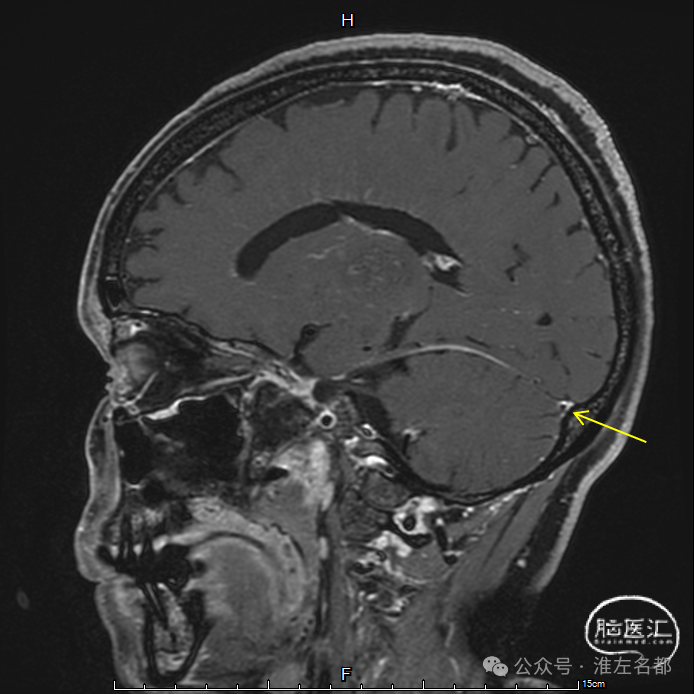

三维黑血高分辨T1

三维黑血高分辨T1平扫(上图)和增强(下图):右侧乙状窦慢性血栓,平扫呈等低信号,并显著强化。

三维黑血高分辨T1平扫(上图)和增强(下图):右侧横窦慢性血栓。

三维黑血高分辨T1平扫(上图)和增强(下图):上矢状窦慢性血栓;直窦内新进血栓(急性血栓等低信号,或亚急性血栓高信号,无强化)。

三维黑血高分辨T1平扫(上图)和增强(下图):左侧横窦发育细小。

三维黑血高分辨T1平扫(上图)和增强(下图):左侧乙状窦局部未发育。